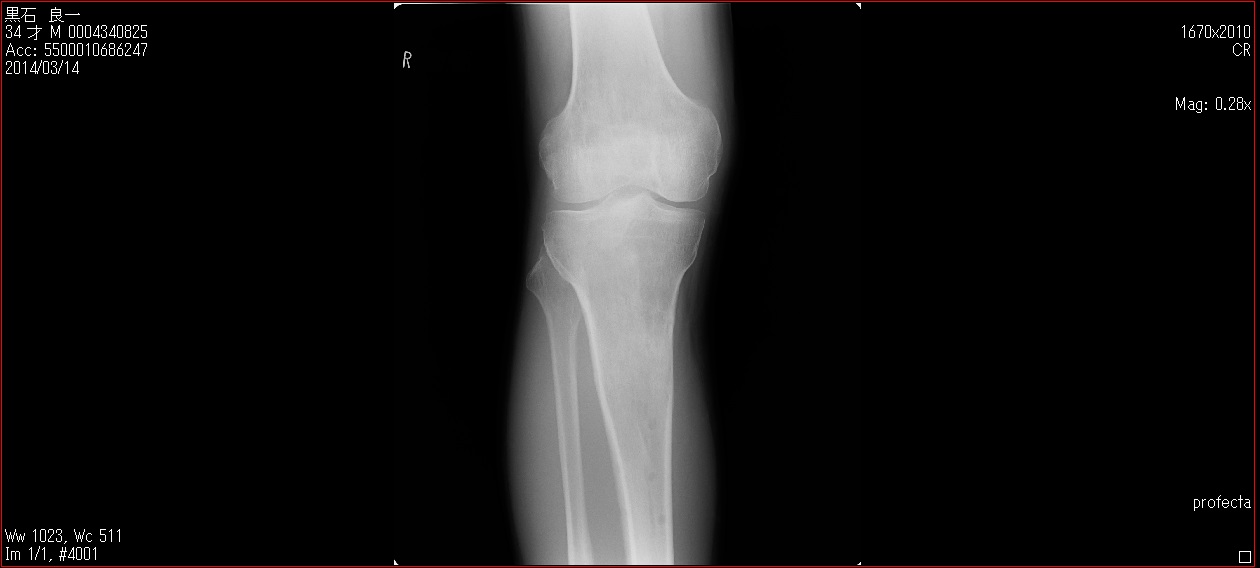

[Ortho] patella baja

Пациент 27 лет приехал для удлинения роста по эстетическим показаниям. Метод: крослатеральное двухэтапное удлинение голеней 4см и бедер 3 см.  Между этапами удлинения уезжал к себе домой в Японию на реабилитацию. Между этапами удлинения движения в коленных суставах разгибание полное сгибание 90-85. После выписки (февраль 2012) даны соответствующие указание постепенно возрастающей нагрузки и ЛФК коленных суставов.

В настоящий момент жалобы на ограничение сгибания в коленных суставах. Снимки прилагаются.

Вопрос: почему возникло такое осложнение? Поверьте приходилось удлинять намного больше, а тут всего на 3-4 см и такое осложнение на обеих конечностях у одного пациента?

Что можно сделать? У кого есть опыт лечения patella baja?